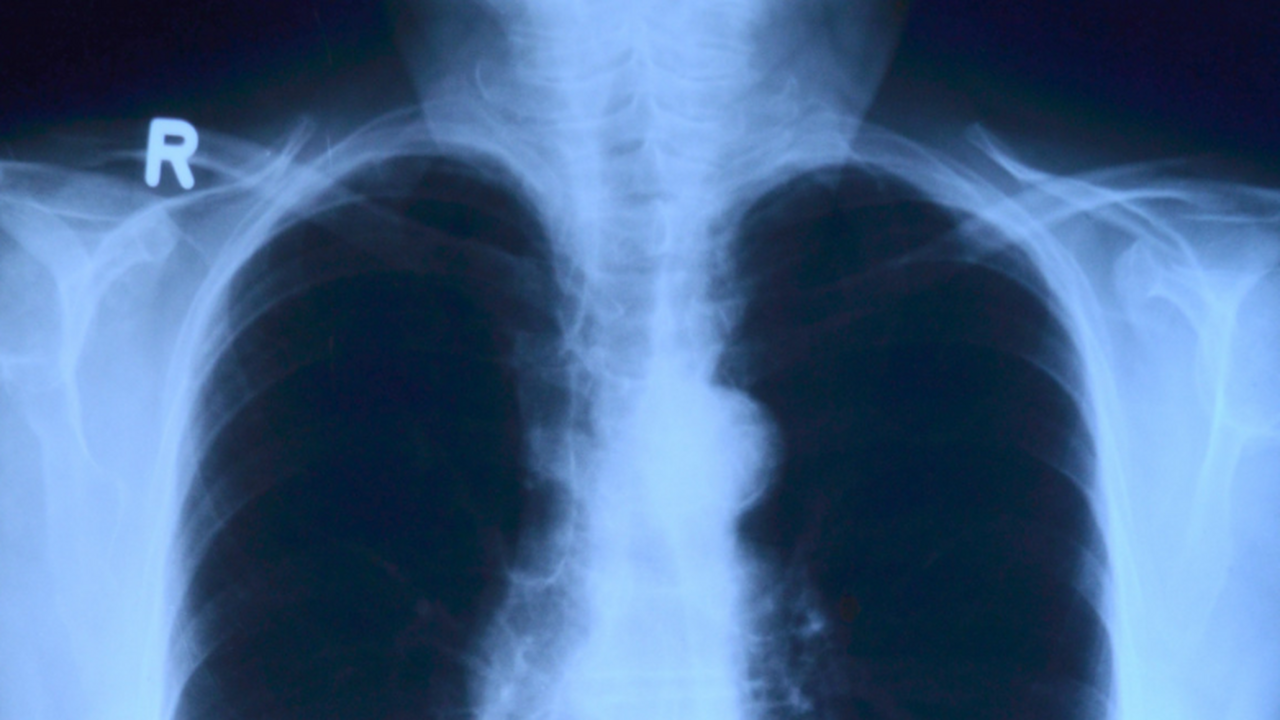

Многие переживают, когда врач назначает рентген или просит повторить флюорографию, — кажется, что организм может получить чрезмерную дозу излучения. Однако специалисты подчёркивают: современные методы лучевой диагностики безопасны, если соблюдать установленные нормы.

Во время исследования человек действительно получает небольшую порцию ионизирующего излучения, однако её значение зависит от зоны обследования и модели аппарата. Так, флюорография грудной клетки даёт примерно 0,6–0,8 мЗв, плёночный рентген — 0,15–0,4 мЗв, а цифровой — всего 0,03–0,06 мЗв.

Санитарные правила устанавливают предел — не более 1 мЗв в год. Это означает, что цифровой рентген грудной клетки теоретически можно выполнить до 20 раз, хотя в реальной практике столько исследований обычно не требуется.